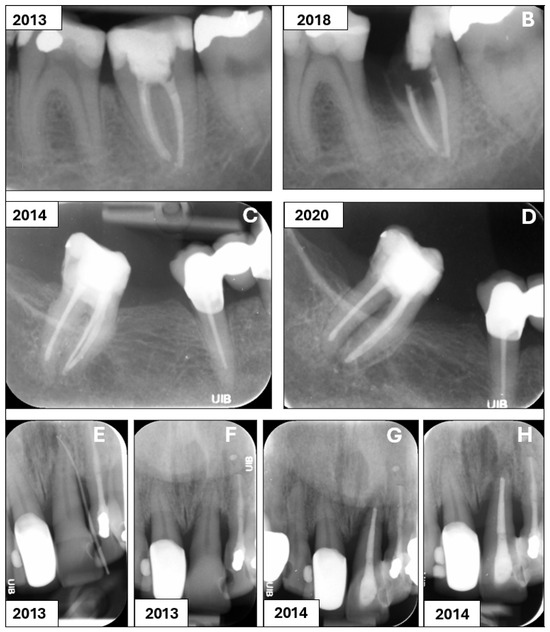

Interesting Images

Palatal Abscess of Endodontic Origin with Extensive Radiolucency in Maxillary CBCT Imaging

by Diana Marian, George Dumitru Constantin, Ademir Horia Stana, Ioana Elena Lile, Tareq Hajaj and Otilia Lavinia Gag (Stana)

Palatal abscesses of endodontic origin are rarer than buccal ones due to maxillary anatomy. Their clinical appearance may resemble that of other palatal illnesses, complicating diagnosis and treatment. Prevention of problems requires early detection and endodontic treatment. A 26-year-old female patient presented with [...] Read more.

Palatal abscesses of endodontic origin are rarer than buccal ones due to maxillary anatomy. Their clinical appearance may resemble that of other palatal illnesses, complicating diagnosis and treatment. Prevention of problems requires early detection and endodontic treatment. A 26-year-old female patient presented with a 2 cm diameter palatal abscess, significant pulsatile discomfort, fever, and enlargement of the anterior hard palate. Clinical examination showed grade 1 mobility of the central and lateral incisors, percussion discomfort, and negative pulp vitality in the case of the lateral incisor. Cone-beam computed tomography (CBCT) showed two radiolucent lesions: a posterior cystic lesion near the first molar and an anterior lesion near the upper left lateral incisor. Palatal cortical bone puncture and soft tissue extension indicated the abscess origin. According to the clinical and imaging evaluation, the upper left lateral incisor had a persistent periapical lesion of endodontic origin that a palatal abscess with cortical bone perforation had exacerbated. Full article